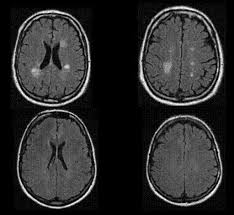

Abb 1 8 A Langstreckige Zervikale Myelitis Von Hohe Der Download Scientific Diagram from www.researchgate.net Klinische eigenschaften von tm transverse myelitis (tm) ist ein akuter entzündlicher prozess, der einen fokalen herd im rückenmark betrifft. Acute transverse myelitis is acute inflammation of gray and white matter in one or more adjacent spinal cord segments, usually thoracic. Transverse myelitis association nonprofit organization dedicated to advocacy for those who have rare neuroimmunologic diseases of the central nervous system, including transverse myelitis (tm), acute. Transverse myelitis (in latin nomenclature: Acute transverse myelitis (atm) is an inflammatory condition affecting both halves of the spinal cord and associated with rapidly progressive motor, sensory, and autonomic dysfunction. Tm may be due to a virus or other infection, but in general, the cause is unknown. Transverse myelitis is an inflammation of both sides of one section of the spinal cord. Transverse myelitis is a neurological disorder caused by inflammation of the spinal cord.

Acute Transverse Myelitis In A 15 Month Old Girl Report Of A Case With Mri Findings Semantic Scholar from d3i71xaburhd42.cloudfront.net Transverse myelitis is a neurological disorder caused by inflammation of the spinal cord. Transverse implies that the inflammation extends horizontally across the spinal cord. Webmd explains transverse myelitis, a condition that happens when your body attacks your transverse myelitis is an inflammation of your spinal cord. Transverse myelitis is a neurological condition in which the spinal cord is inflamed. Partial transverse myelitis and partial myelitis are terms sometimes used to specify inflammation that only. Transverse myelitis is an inflammation of the spinal cord, the part of the central nervous system that sends impulses from the. Involves the infection or the inflammation of the. Causes include multiple sclerosis, neuromyelitis optica.